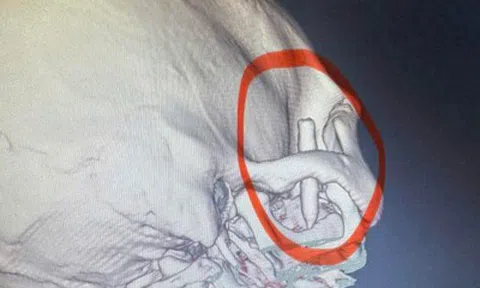

Điều đáng nói trước đó đầu tháng 3/2026 tại xã Phước Năng cũng xảy ra 3 trường hợp là trẻ em bị ngộ độc botulinum sau khi ăn cá ủ chua.

Sau đó Tổ chức Y tế thế giới (WHO) hỗ trợ khẩn cấp thuốc giải độc Botulism Antitoxin Heptavalent cho Đà Nẵng để điều trị cho các bệnh nhân ngộ độc.

Theo Sở Y tế Đà Nẵng, đây là loại thuốc đặc trị rất hiếm và đắt đỏ, mỗi lọ có giá khoảng 8.000 USD, hiện chưa có sẵn trong nước. Trước tình huống ba bệnh nhi nguy kịch, ngành y tế thành phố đã báo cáo và phối hợp với Bộ Y tế để kết nối với WHO đề nghị hỗ trợ khẩn cấp.

Nhờ sự phối hợp nhanh giữa các đơn vị trong và ngoài nước, chiều 11/3 ngành y tế Đà Nẵng đã tiếp nhận thuốc và ngay trong tối cùng ngày chuyển đến bệnh viện để kịp thời sử dụng cho bệnh nhân.